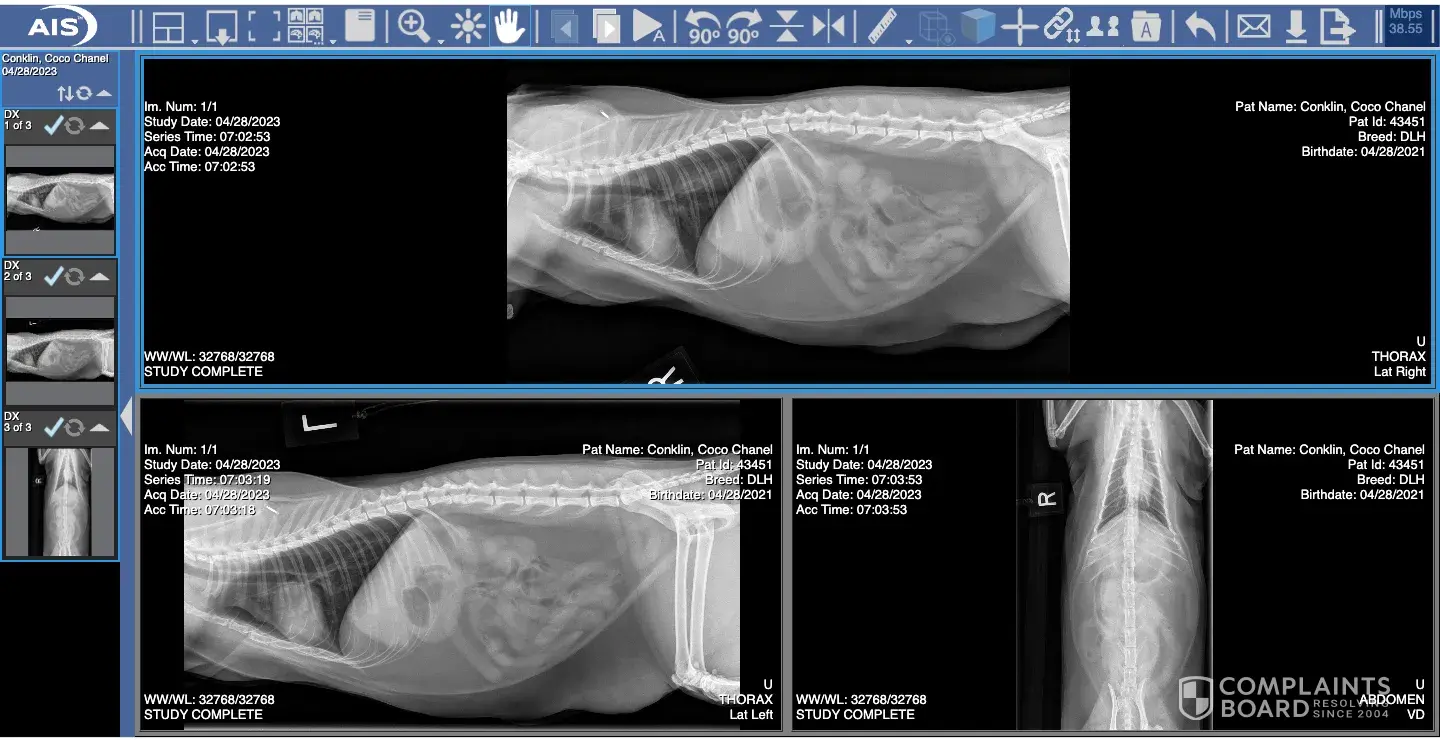

I purchased a kitten from Lyn Milstead of Jollytime Ragdolls here in Salisbury, North Carolina, on June 7, 2021 for $2500. The kitten quickly became a part of our family and was well loved. However, things came to an abrupt end when the kitten was rushed to the Cabarrus Emergency vet on April 28, 2023. She had just turned two and I had no idea what was happening. She was acting strange. The vet’s office took lab work and x-rays. The lab work was then transferred to another hospital to see if they would be able to determine a cause. The vet at Cabarrus Animal Hospital, Dr. Barbee, explained to me that my cat, Coco Chanel, had a congenital heart defect. She determined this because the x-rays the emergency vet took showed a good heart, but the x-rays they took an hour later showed and enlarged heart and lungs filled with fluid. They did everything they could to keep her alive, but she soon passed. I was absolutely devastated. I left the office with my empty cat carrier.